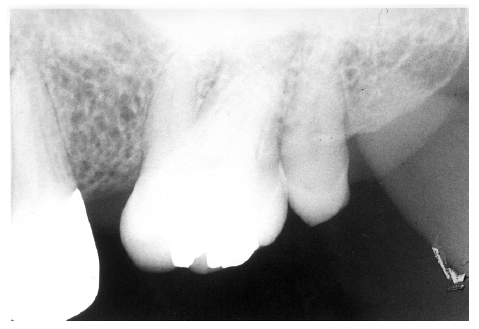

Figure 2 illustrates advanced enamel caries on the mesial surface of the premolar.

Figure 2 - Advanced Enamel Caries

Figure 2